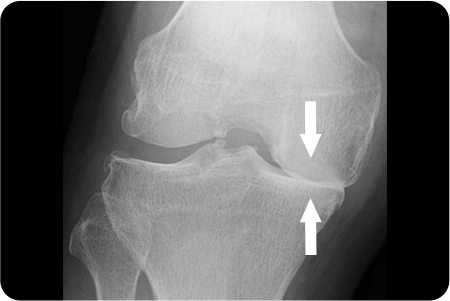

퇴행성관절염으로 연골이 마모되고 관절이 내려앉게 되어

진행된 휜 다리(O 다리, X 다리)를 바르게 교정하여

무릎 내 외측에 집중되어 있는 무게 중심을

고르게 분산시켜 관절염의 진행을 막는 수술법

입니다.

무게 중심이 내측으로

쏠려 있는 O다리 수술

경골을 절골하여 원하는 각도로 벌려 무게 중심이

바깥쪽으로 옮겨지도록 교정

합니다. 절골한 부위를

금속판과 나사로 고정해 뼈가 안정적으로 붙도록 합니다.